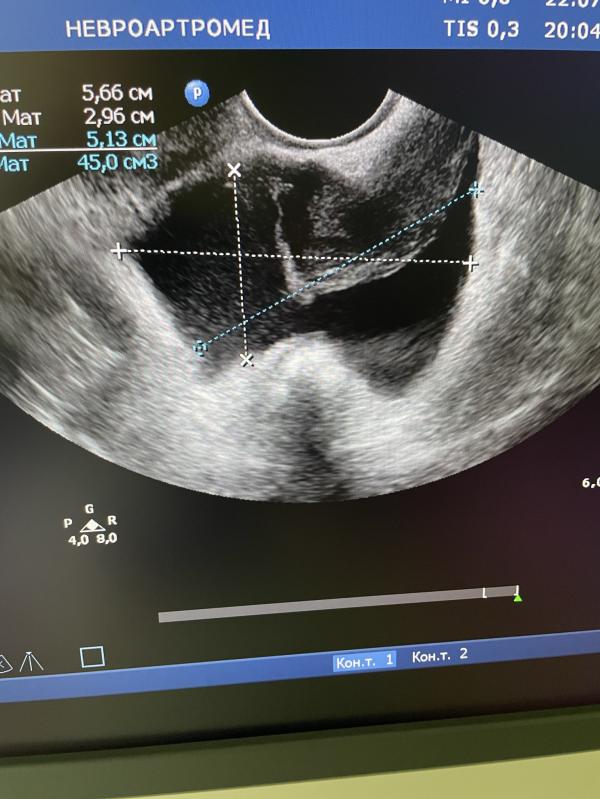

Экссудат в малом тазу с незначительной взвесью: что это значит и какие могут быть причины?

Экссудат в малом тазу с незначительной взвесью.